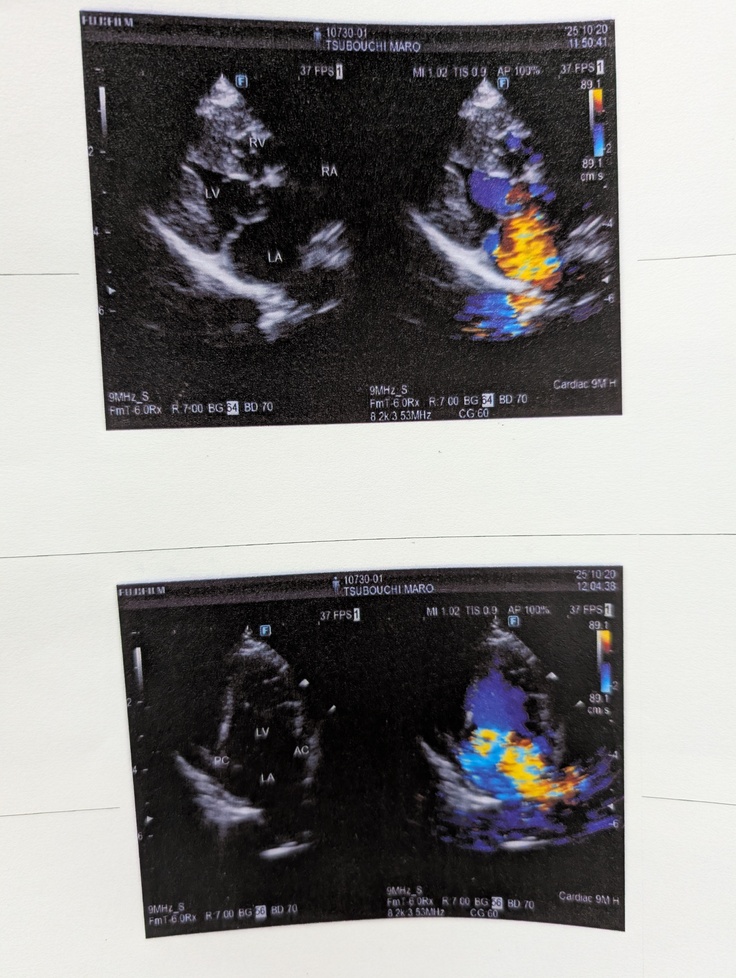

採血の心エコー検査の他にも、腹部エコーや心電図もやっております。

心臓の手術適応かどうかの検査を行う。検査の結果心臓以外の異常は見られず、先生からは現在ステージCであること、手術は今がベストであると説明を受ける。